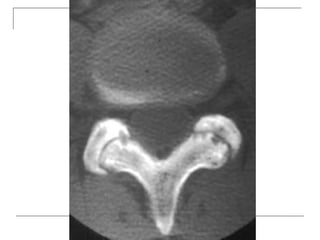

CT Scan

 better visualization of bone pathology (eg.

cortical destruction)

 fracture

 tumor